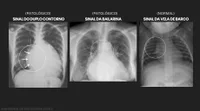

Quais os sinais radiológicos presentes na imagem?

Sinal do timo e sinal da bailarina

Sinal do duplo contorno e sinal da bailarina

Sinal da vela do barco e sinal da onda